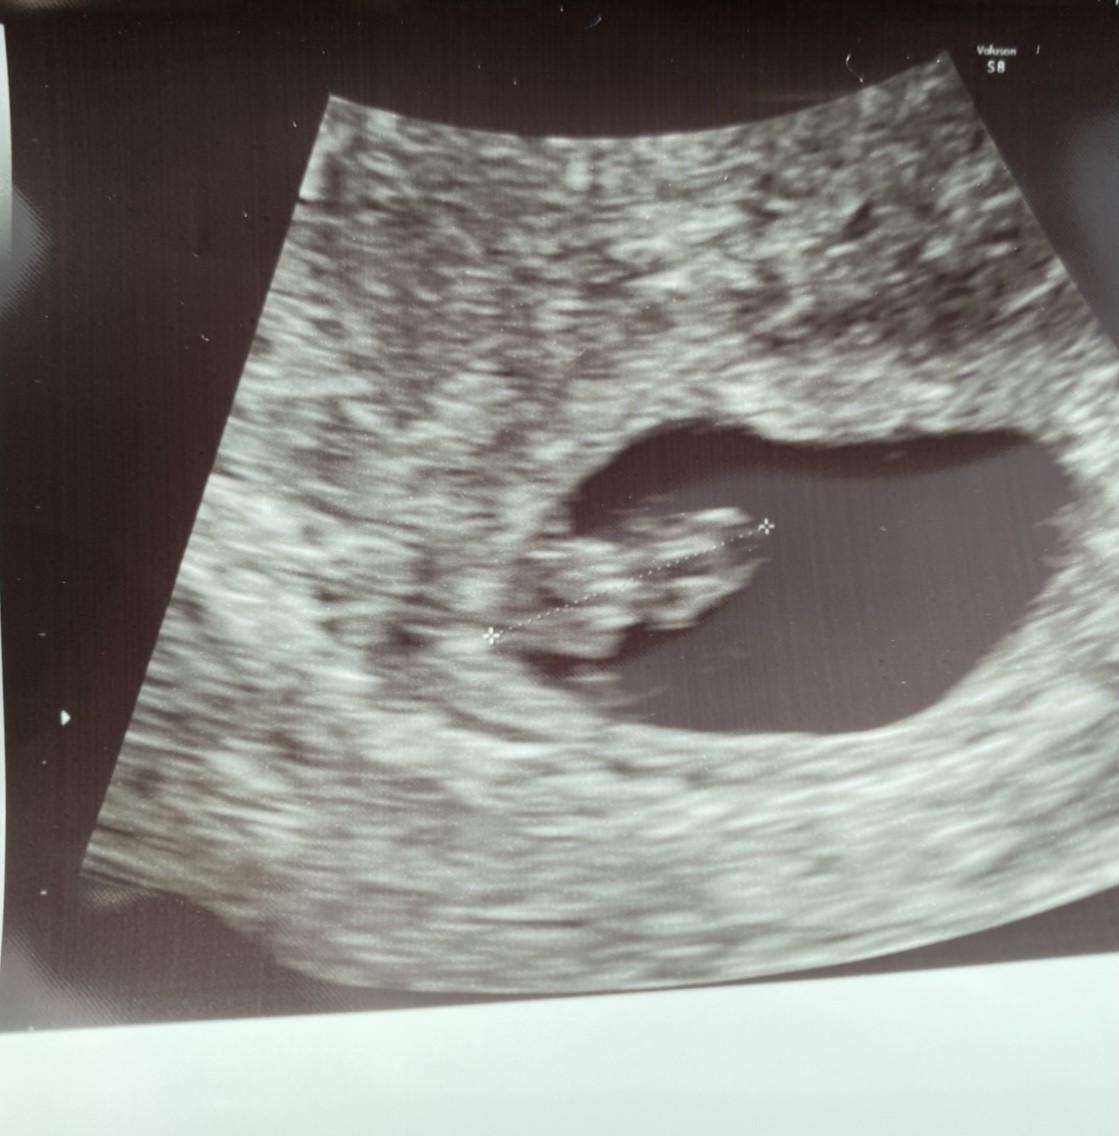

Ale mały wielki cudZobacz załącznik 1254177Bejbik rosnie pieknie, juz ma 12,5mmna ta chwile zakonczylismy nasza kariere z klinika nieplodnosci, jestesmy przeszczesliwi

Śliczny człowieczekJuż po wizycie ... dzidzia już nie wyglada jak fasolkaNa dzień dzisiejszy wSzytsko wyglada bardzo dobrze

Też mam następną wizytę w podobnym terminie (będzie 9+3) i też mam nadzieję na taki widokNo cudny dzidziulekjuż wiem czego mogę się mniej więcej spodziewać na mojej wizycie 9+4